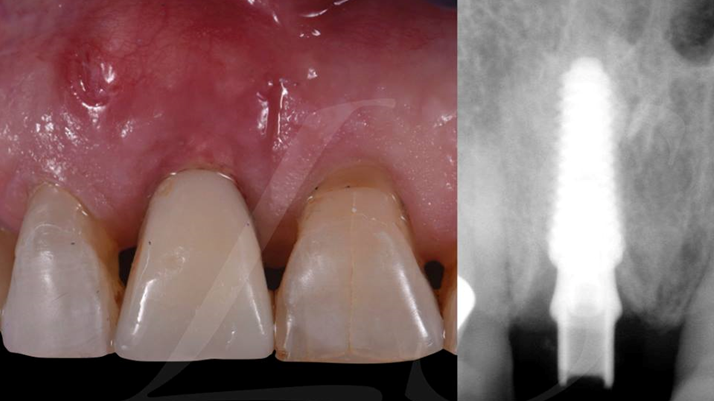

“ One implant /One tooth/ One hour step-by-step

+ associated connective graft ”

Clinical case: EImmediate implant placement & loading of #35 extraction socket with defect

- Courtesy of Dr. Kwang Bum Park, Korea -